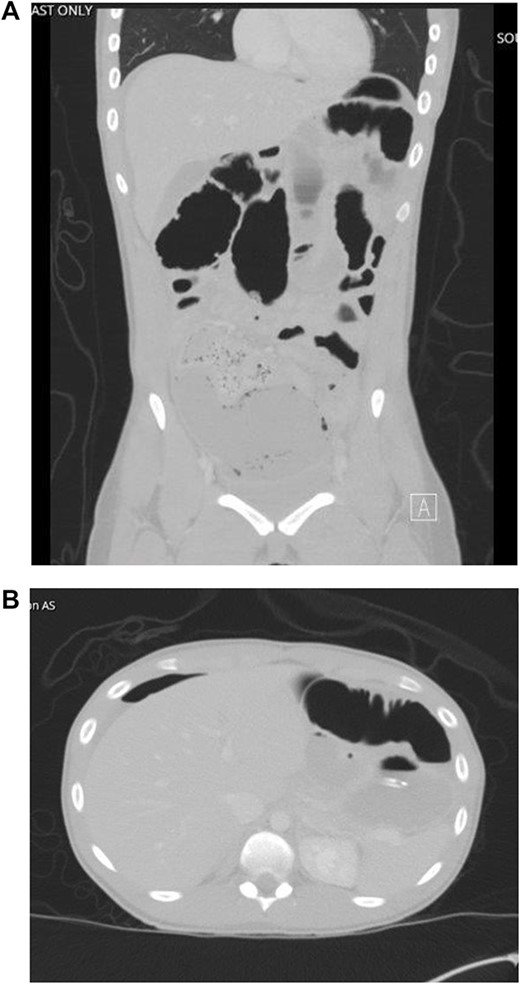

Patient is a 21-year-old female who presented with severe, sudden onset abdominal pain with associated poor oral intake, nausea and vomiting. Patient’s only past medical history was remarkable for normocytic anemia found on lab work. Patient did not report any significant family history. As a part of the patient’s initial work-up a computed tomography (CT) of the abdomen and pelvis with IV contrast was obtained with evidence of intussusception of a long segment of small bowel in the lower midline abdomen extending into the pelvis, measuring ~15 cm in length (Fig. 1); the patient’s CT was not remarkable for pneumatosis or obstruction.